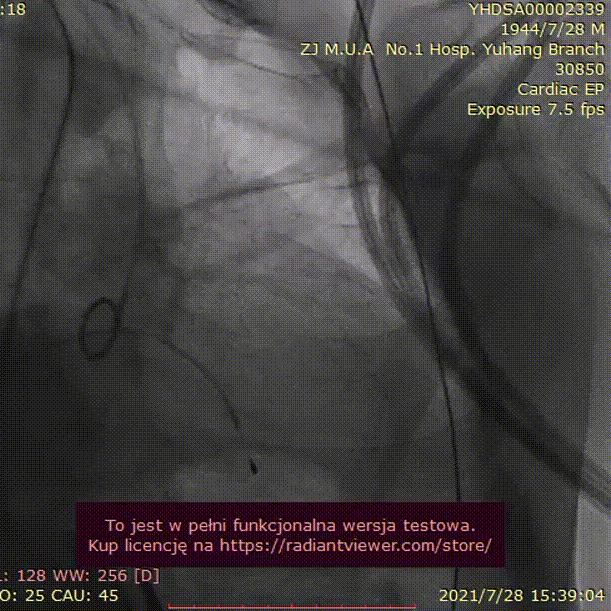

手术过程:

23mm球囊预扩

(有腰征,无瓣周漏,右冠开口阻塞)

TAV24 瓣膜释放前定位

释放4.0*30mm烟囱支架

植入后造影

术后压差1mmHg

术中经食道心超评估: